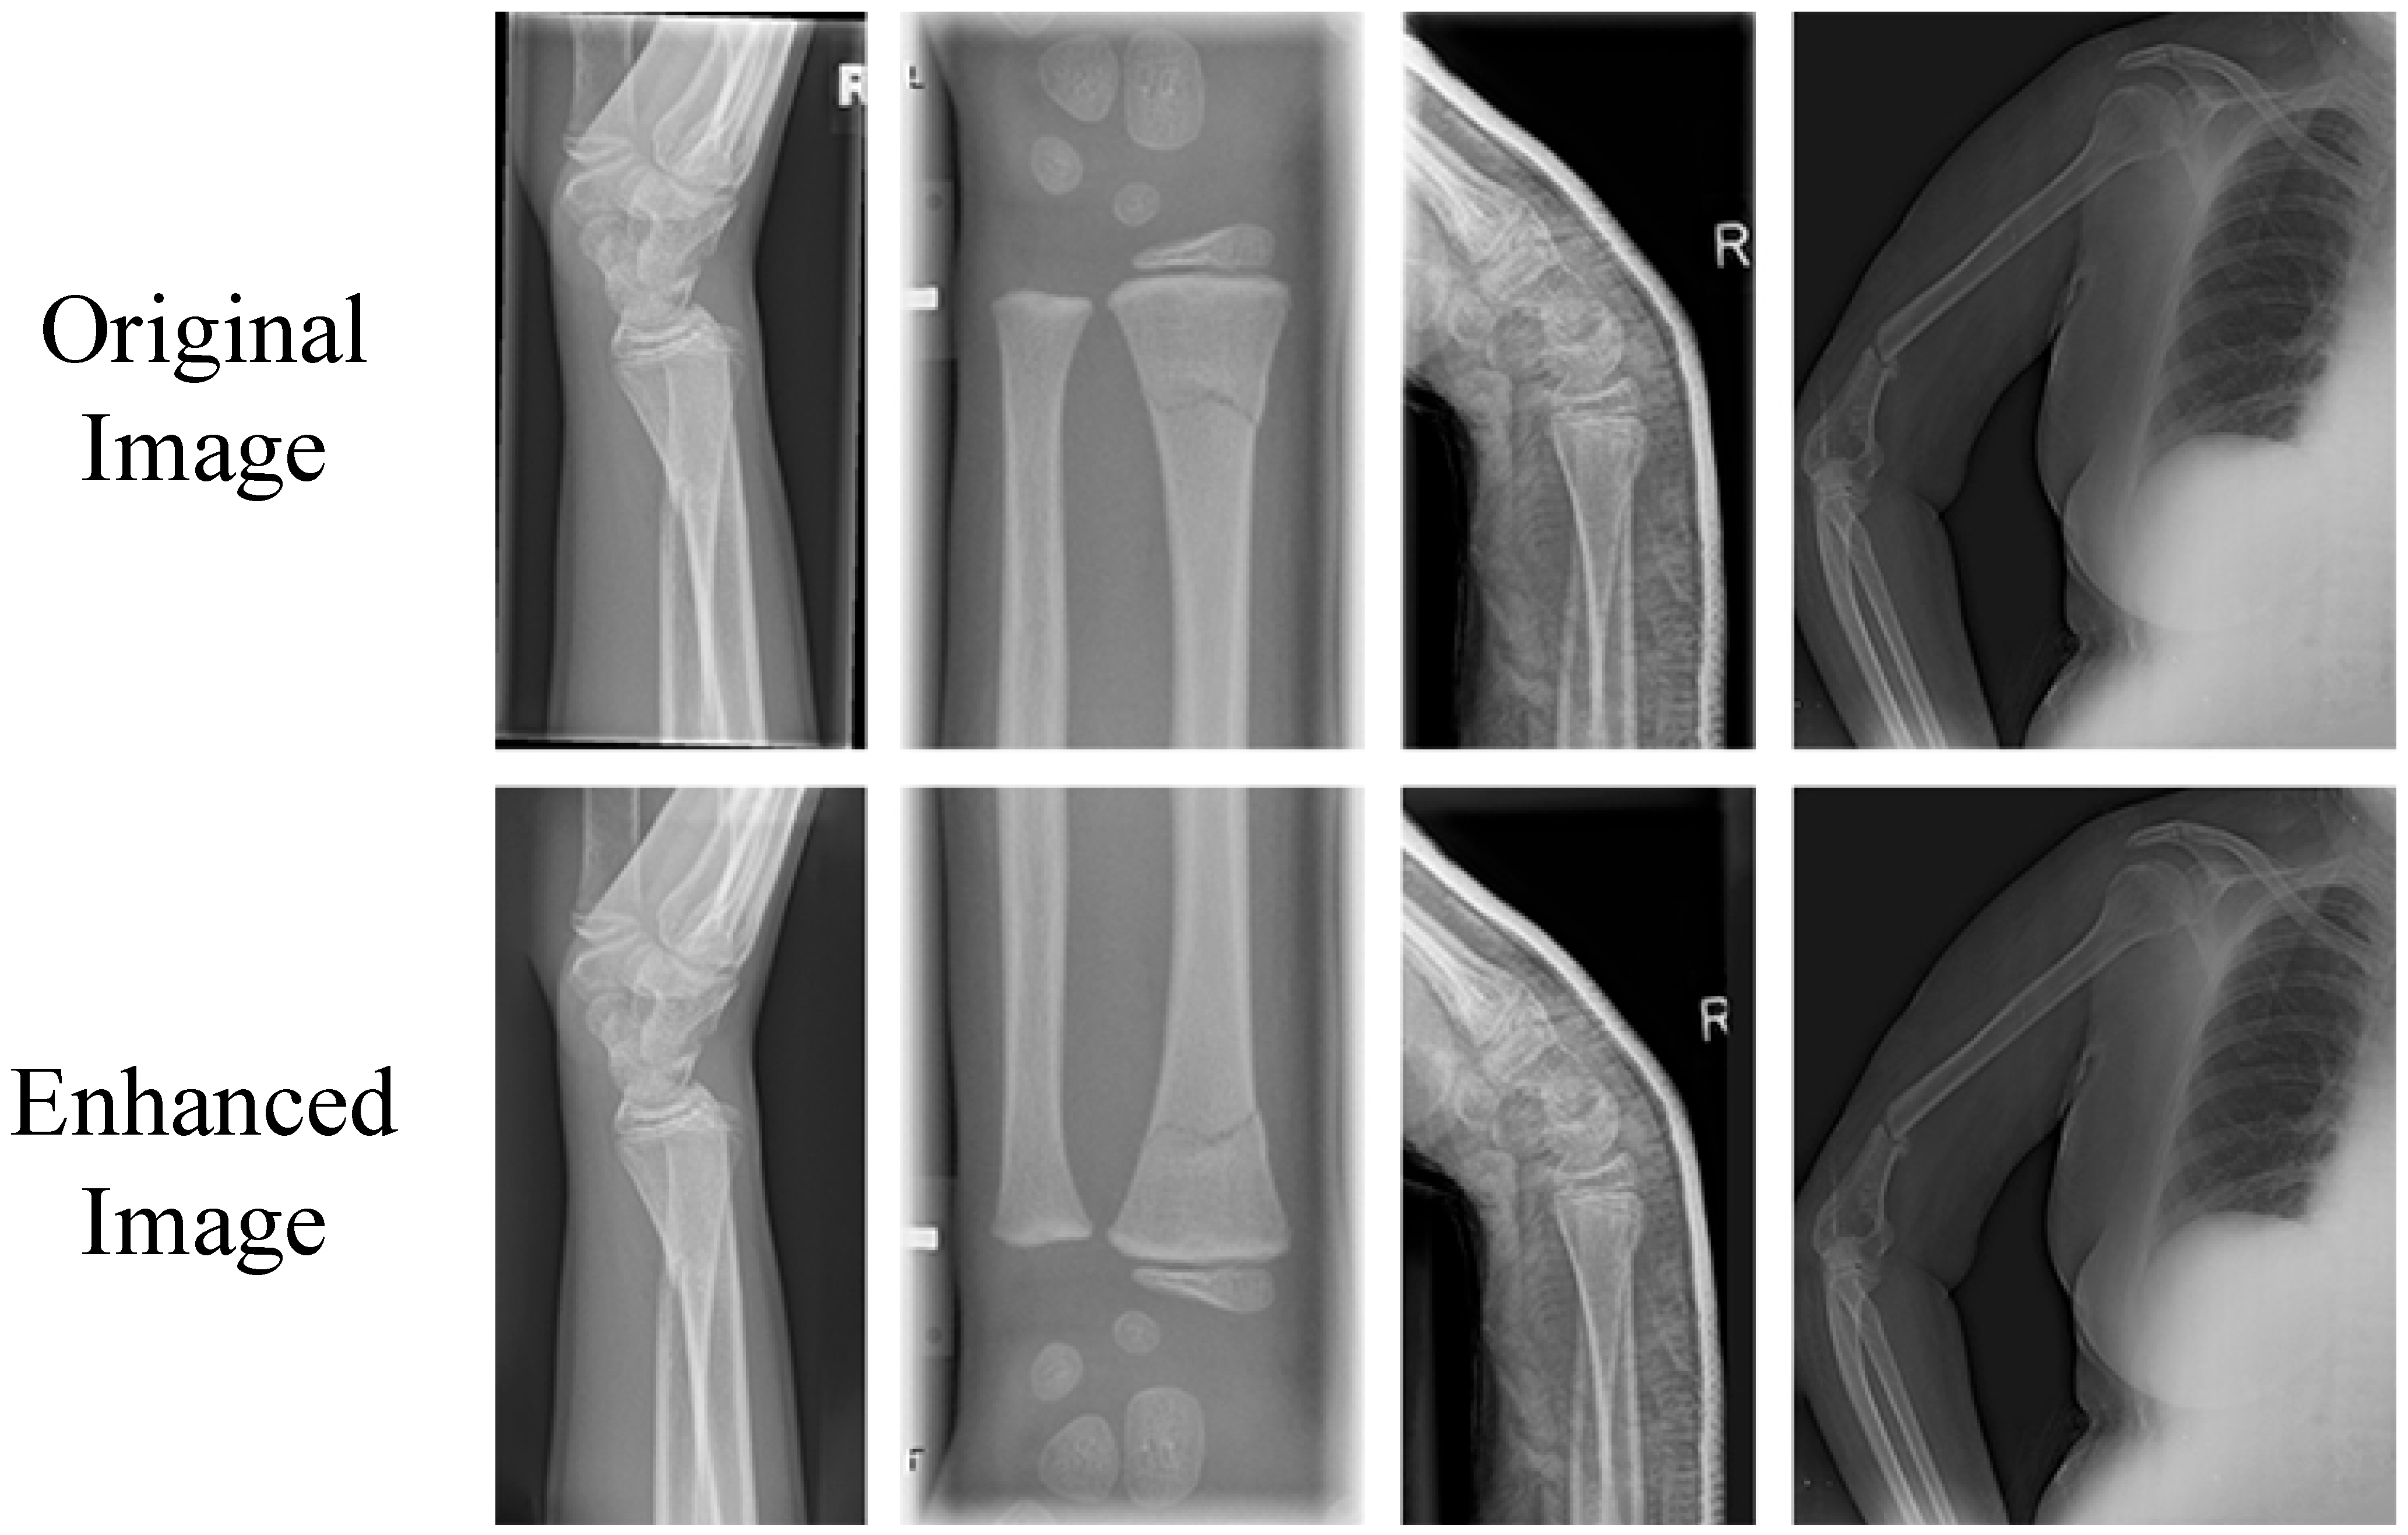

- First of all, multiple public datasets were collected. Subsequently, a data augmentation technique combining random rotation, translation, flipping, and content recognition filling was proposed. This was performed to effectively alleviate the problem of data scarcity and thereby enhance the generalization ability of the model.